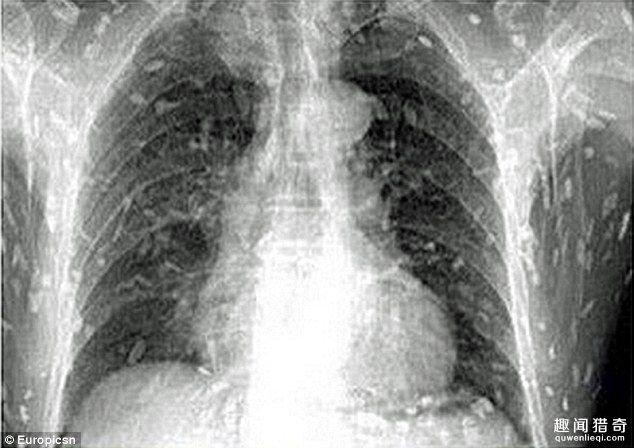

相信不少人都非常喜歡吃生魚片,近日,一名男子卻因為過度食用生魚片而差點喪命。 據報道,這名男子因為腹痛和皮膚瘙癢而前去醫院就診,在X光下顯示了這駭人的一幕。

這名男子的身上已經全是寄生蟲,看了讓人頭皮發麻。 醫生認為他是因為吃了太多的生魚片,才會有如此嚴重的感染。 目前他正轉往廣州市第八人民醫院接受治療。

研究顯示吃生肉或者生魚都有感染寄生蟲的風險。如果通過食用像鮭魚等魚類吃下寄生蟲幼蟲的話,就會有絛蟲感染的風險。 絛蟲感染的案例在發展程度較高的國家也逐年增加,醫生推測這是因為壽司和生魚片普及程度越來越高的原因。